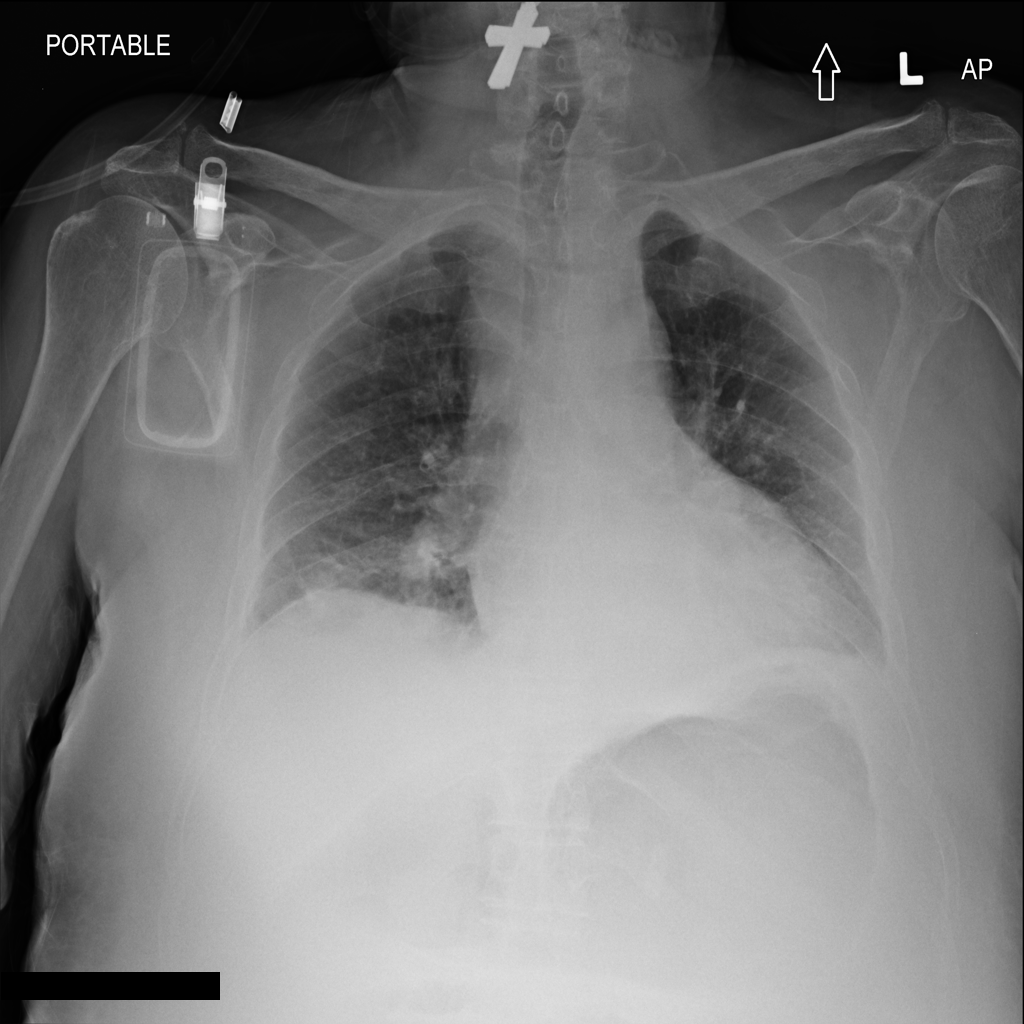

We conclude our analysis with consideration of the ChestXray-14 [RIZ+17] dataset. This dataset contains frontal X-ray images labeled with 14 different conditions. ChestXray-14 is a multi-label tagging task (i.e., a single image can have more than one condition), so we treat each condition as its own binary problem. In this section, we focus on the condition Effusion. Results on other conditions can be found in Appendix C.3.

The trained SVM identifies visually distinguishable failure mode directions in latent space. As shown in Figure 11, the representative images flagged by this SVM as most incorrect are blurrier and less bright. Moreover, this trend is not reflected by the least confident images, indicating that our framework is isolating a different trend than the one corresponding to ordering the images by base model confidence.

In fact, we find that the SVM may be picking up on the position in which the exam was conducted. While the majority of the X-rays are Posterior-Anterior (PA) radiographs, a little over a third are Anterior-Posterior (AP). PA radiographs are usually clearer, but require the patient to be well enough to stand [TB20]. Examples of AP and PA radiographs from the dataset can be found in Appendix C.3.

As shown in Table 13, the SVM for the class “no effusion” flags a large number of the AP radiographs as incorrect. This indicates that the model might indeed rely on the position in which the radiograph was taken to predict whether the patient was healthy. Moreover, the SVM selects the AP examples more consistently than ordering the radiographs by the base model’s confidence (Figure 13).